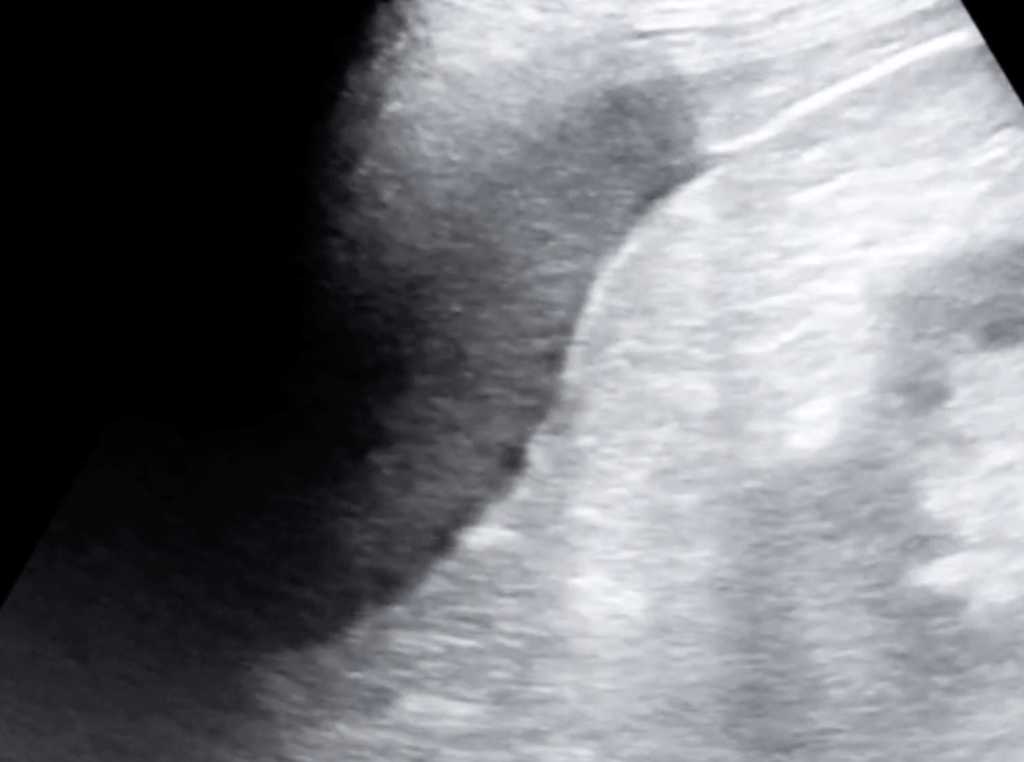

5 Minute Sono

- Large curvilinear probe

- Graded compression up and down

- Diverticula

- Bowel wall>5mm

- Prominent fluid-filled bowel loops

- Pericolic free fluid

- Increased pericolic fat (hyperechoic)

- Abscess